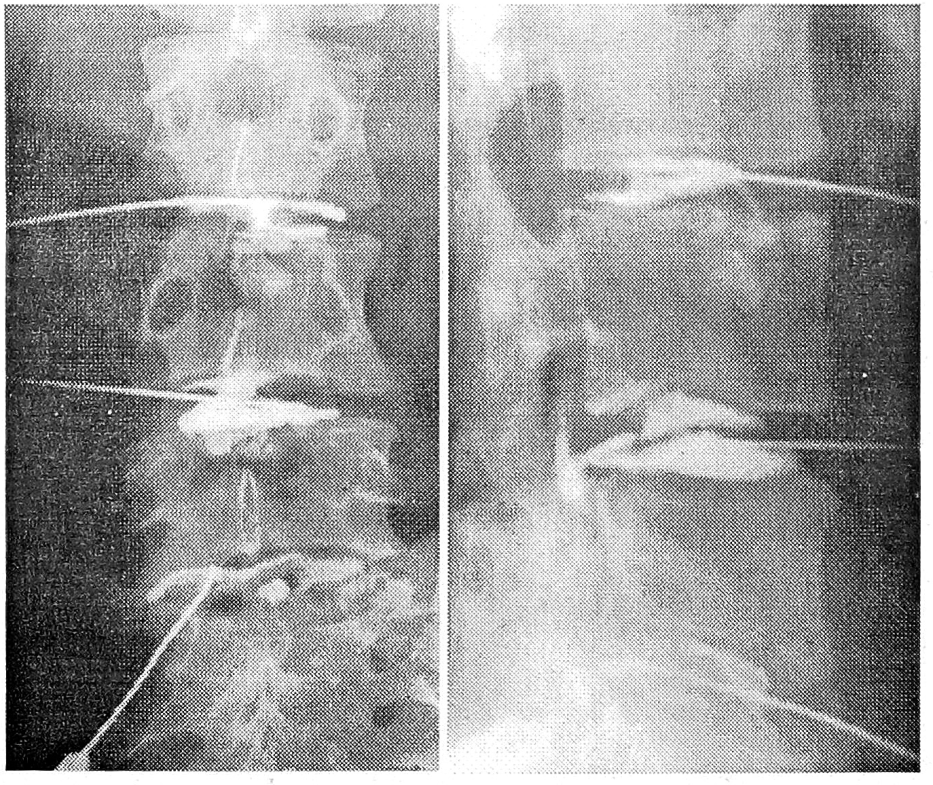

Субламинарный тип диСкограмм регистрировался в позвоночных сегментах с «чисто» клиновидными позвонками и позвонками с относительным увеличением переднезаднего размера тела. На дискограмме определялось контрастирование всех элементов диска с затеканием контрастного вещества под замыкательную пластинку через ее трещины и разрывы. Затекание контрастного вещества носило локальный характер и выявлялось как гомогенная линейная тень длиной не более 4—5 мм. Как правило, контрастировался прилежащий участок замыкательной пластинки. Отмечалось умеренное снижение высоты межтеловых промежутков (см. рис. 9). Емкость диска составляла 1,0—1,5 мл; его инъецирование сопровождалось поясничной болью средней интенсивности.

Рис. 9. Субламинарный тип дискограмм (контрастирование нижних замыкательных пластинок тел L2, L3 позвонков).